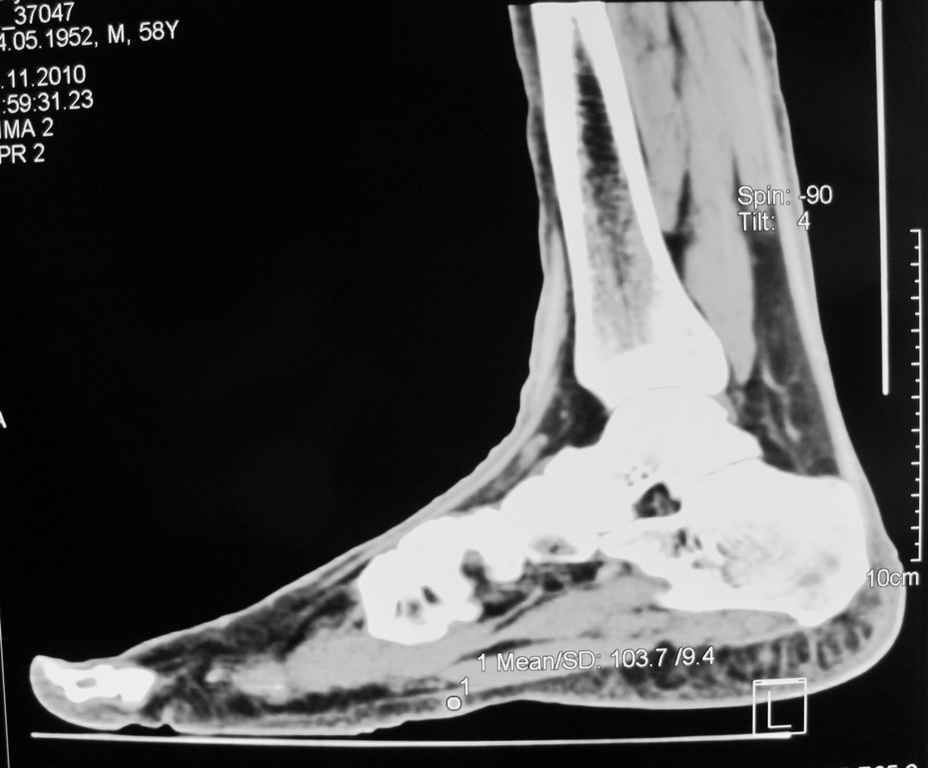

Мужчина 58 л. месяц назад наступил на камень, после того, как прошли боли, почувствовал уплотнение с медиальной стороны правой стопы.

Сделал КТ 02.11.2010 г.

Пальпаторно: определяется уплотнение размеры с горошину (0,3 Х 0,2), при пальпации безболезненно, малоподвижное. Кожные покровы в области уплотнения не изменены.

Мне по снимкам кажется, что это маленькая кальцифицированная гематома. Я бы убрал.